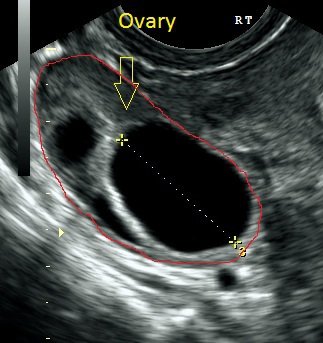

We measure the lining of the womb (endometrium) and measure the follicles within the ovary (which contain the eggs).

The third scan is performed depending on the size of the follicles and they are monitored to inform you when an estimation of ovulation is likely to occur, which in turn increases your chances of conceiving. When the follicle/s are 20 mm they will rupture – this is ovulation.

A further forth scan can be performed after ovulation, a corpus luteal cyst should be present to ensure ovulation has occurred; this will give you an insight of how the ovaries are working within it and whether you are definitely ovulating.